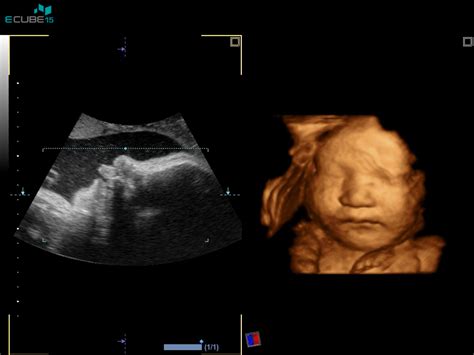

Postopek poteka pod stalnim ultrazvočnim nadzorom:

- Določitev lege posteljice: Zdravnik najprej z ultrazvokom natančno določi lego posteljice in starost nosečnosti z meritvijo ploda.

- Pristop z iglo: Če je dostop do posteljice ustrezen, zdravnik skozi trebušno steno nosečnice z zelo tanko iglo odvzame vzorček tkiva horionskih resic.